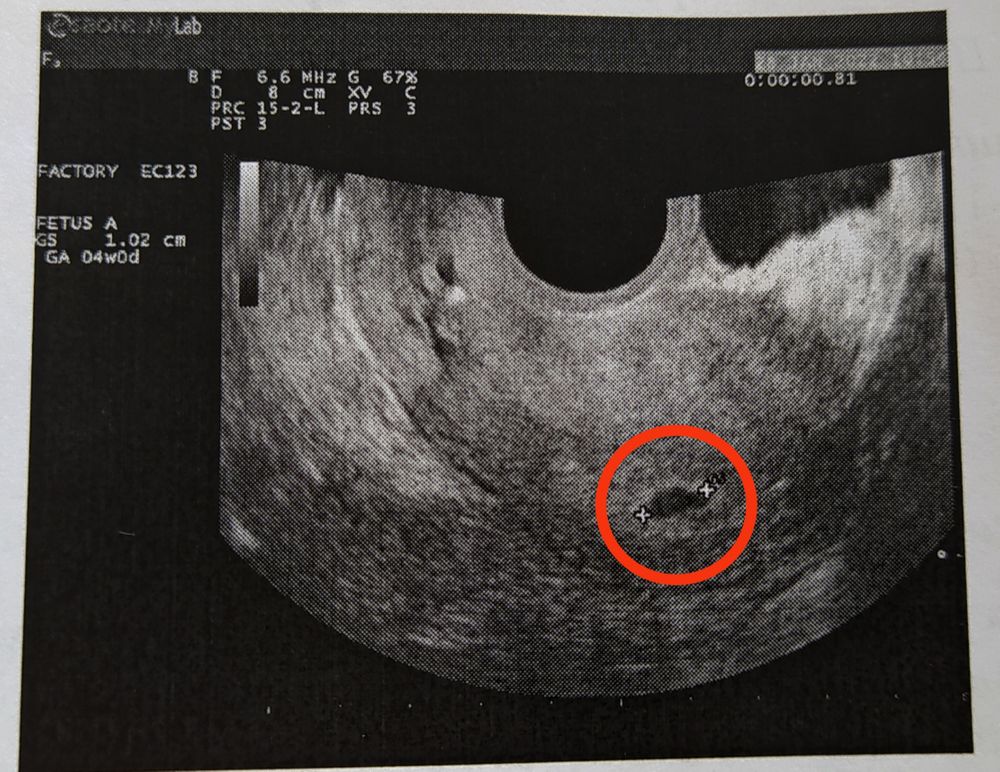

4 эмбриональные недели узи

4 эмбриональные недели узи 148 фотографий